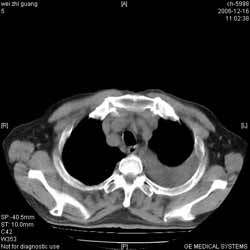

診斷方法

關於膀胱小細胞癌的診斷,對於臨床醫生和病理科醫生來說仍是比較困難的。確診主要還是依靠組織學檢查,包